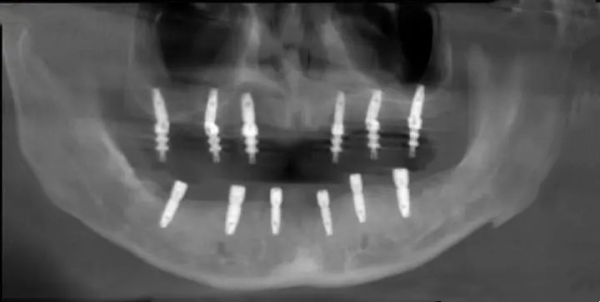

A. 核心技术:S.L.A.表面处理

档次的高低,首先看表面处理。八维采用的是主流的大颗粒喷砂加酸蚀技术(S.L.A.)。这种技术能让植体表面产生微孔结构,就像在泥土里撒了助长剂,让牙槽骨细胞能快速“爬”上去并紧紧抓牢。这意味着它的骨结合速度快,大大缩短了戴冠的等待期。m.59=w.net

B. 材质与强度:四级纯钛的坚持

八维植体选用的是医用四级纯钛。在金属学里,四级钛的机械强度和生物相容性达到了黄金平衡点。既可能会了植体不会在长期咀嚼中发生断裂,又确保了人体不会产生排异反应。

C. 设计细节:微螺纹与锥形连接

它的设计考虑到了东方人牙槽骨相对偏窄、偏软的特点。顶部的微螺纹设计能有效分散咬合压力,防止骨吸收(也就是防止牙龈萎缩导致植体暴露),这对于延长植体寿命至关重要。